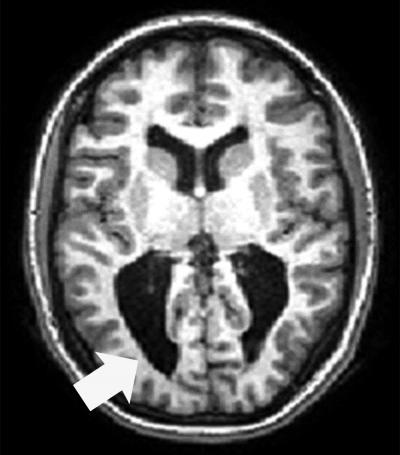

Magnetic resonance imaging scan shows an adolescent with CVI associated with prematurity. Enlarged ventricles with irregular sulcal patterns (folds) in the occipital pole (a hallmark sign of periventricular leukomalacia, PVL) are apparent (arrow). Credit: Lotfi Merabet

Complications from premature birth are one of the leading causes of CVI. During the second half of pregnancy the brain is rapidly developing, making it particularly vulnerable to certain types of injury such as periventricular leukomalacia (PVL). PVL is associated with damage to the developing neurons and support cells in many parts of the brain, especially in areas responsible for motor function and visual processing. As a result, infants with PVL have a higher likelihood of developing cerebral palsy and CVI.